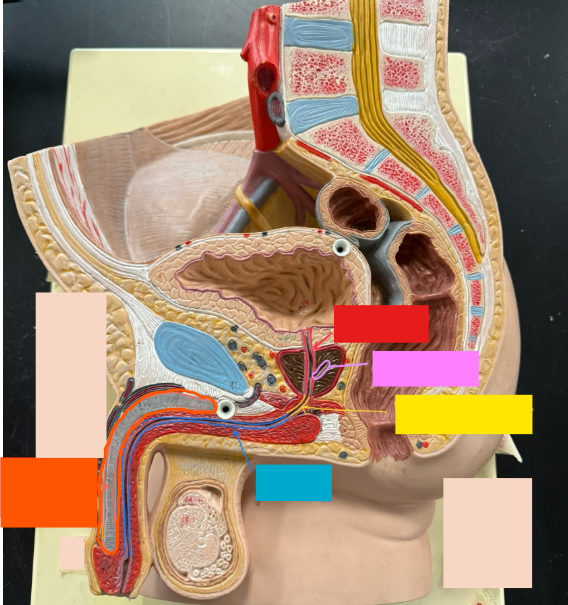

What is the name of the red box?

Ureter

What is the name of the red box?

Vas deferens

What is the name of the yellow box?

Seminal vesicle

What is the name of the blue box?

Prostate

What is the name of the light blue box?

Prepuce

What is the name of the blue box?

Corpus spongiosum

What is the name of the black box? X2

Prostate

What is the name of the purple box?

Rectum

What is the name of the yellow box?

Anus

What is the name of the red box?

Prostatic urethra

What is the name of the pink box?

Ejaculatory duct

What is the name of the yellow box?

Membranous urethra